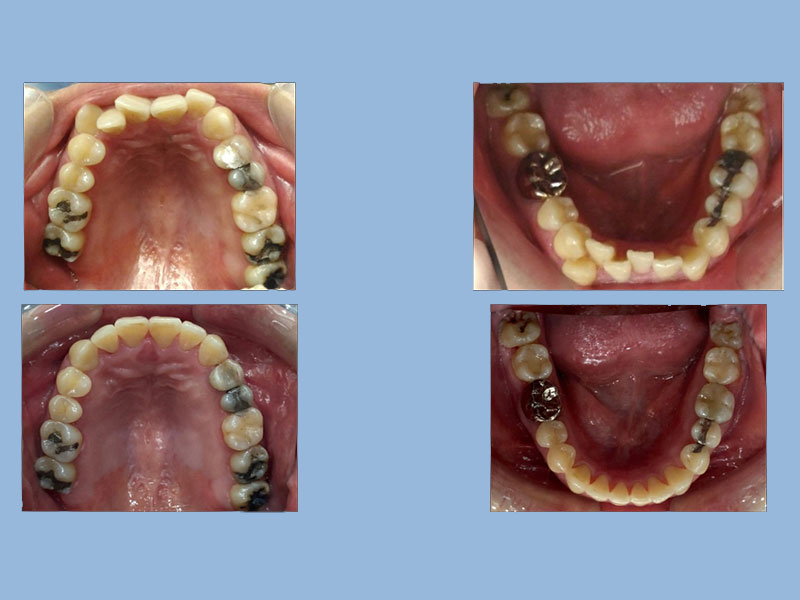

萬先生 (37歲) 矯正完成

狀態 : 門牙歪、擠、缺牙、植牙、沒拔牙